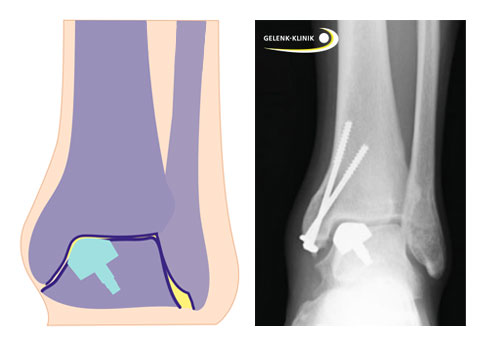

Teilprothese für das Sprungbein:

- passgenaue Teilprothese für den geschädigten Anteil am Sprungbein

Teilprothese am oberen Sprunggelenk

Die Teilprothese am oberen Sprunggelenk ersetzt nur den geschädigten Gelenkteil des Sprungbeins (Talus). So kann der Patient eine TEP (Totalendoprothese) vermeiden. Das Teilimplantat ersetzt jedoch nicht nur den zerstörten Gelenkknorpel metallisch, sondern auch den darunter liegenden geschädigten Knochen. Die individuell angefertigte Teilprothese stellt die Gelenkoberfläche des Talus möglichst exakt wieder her, damit der dort aufliegende Gelenkknorpel des Schienbeins intakt bleibt.

Wann eignet sich eine Teilprothese am Sprunggelenk?

Häufig wurden die Patienten, für die ein Teilersatz des Sprungbeins in Frage kommt, mehrfach wegen einer osteochondralen Läsion voroperiert. Der Aufbau des geschädigten Knorpel-Knochen-Areals mit biologischen Maßnahmen war nicht zufriedenstellend und die Patienten leiden weiterhin unter Schmerzen und einer eingeschränkten Funktion des Sprunggelenks.

Ist der Schaden am Sprungbein auf ein bestimmtes Areal begrenzt, empfehlen die Spezialisten für Fuß- und Sprunggelenkchirurgie diesen Patienten den Einsatz einer Teilprothese. Der Teilersatz überdeckt den Defekt am Knochen vollständig und stellt die Oberfläche des Sprungbeins als wesentlichen Anteil des oberen Sprunggelenkes optimal wieder her.

Wie stellt der Spezialist die präzise Herstellung des individuellen Implantates sicher?

Jede Teilprothese wird an die individuelle Anatomie des Patienten angepasst und durch spezialisierte Konstrukteure hergestellt. Die Planung der Teilprothese erfolgt durch die Fuß- und Sprunggelenksspezialisten der Gelenk-Klinik. Neben Information zur Knorpel- und Knochensituation am Sprunggelenk fließen auch Informationen über den bisherigen Krankheitsverlauf und mögliche Voroperationen aufgrund zusätzlicher Schäden am Sprunggelenk ein. So erhält jeder Patient ein individuelles Implantat.

Vor der Produktion der Teilprothese und des benötigten Werkzeugsets durch die Konstrukteure überprüft der Spezialist mit dem Patienten das Design, da die Teilprothese und das Instrumentarium nur für diesen Patienten verwendet werden können.

Design der Teilprothese für das Sprunggelenk

Das spezielle Design der Teilprothese besteht aus einer Kobalt-Chrom-Legierung und ist mit Titan und Hydroxylapatit beschichtet und aufgeraut. Das Material und der Zapfen ermöglichen nach dem Einbau eine optimale Fixierung, bis der Teilersatz fest mit dem gesunden umgebenden Knochen verbunden ist. Die Oberfläche (Kappe) ist ultraglatt poliert und steht mit dem Schienbeinknorpel in direktem Kontakt.